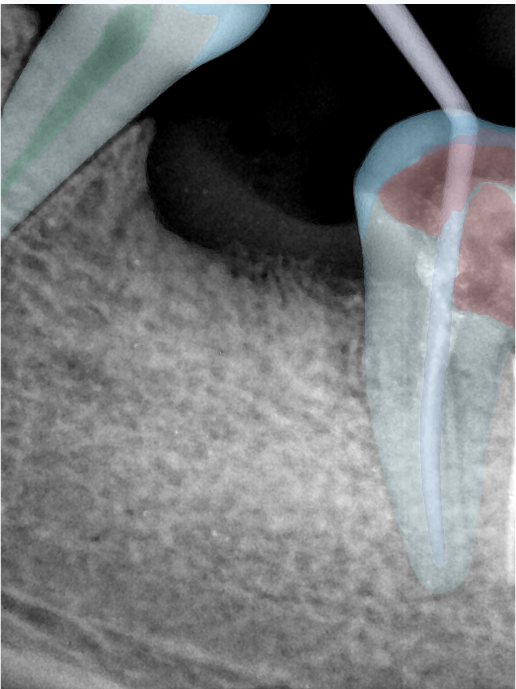

第二版算法问题测试

| 第一版 | 第二版 | 是否解决 | |

|---|---|---|---|

![]() | ![]() ![]() 边角识别有问题 龋齿识别不全 牙髓识别不全 | ![]() | 解决 |

![]() | ![]() 边角识别有问题 识别信息有误 自查(牙冠识别不全) | ![]() | 解决 |

![]() | ![]() ![]() 边角识别有误 大范围填充识别遗漏 | ![]() | 解决 |

![]() | ![]() 识别信息不全 | ![]() | 解决 |

![]() | ![]() ![]() 边角问题 牙胶识别不全 牙冠识别不全 | ![]() | 解决 |

![]() 换图片 | ![]() | ![]() 牙冠部分稍微白了一些就识别成小范围修补,部分判断异常 | 部分解决,修复类略敏感,牙冠部分稍微白了一些就识别成小范围修补,部分判断异常。 |

![]() | ![]() ![]() 牙冠识别不全 牙髓不全 根尖炎龋齿识别有误 | ![]() | 解决 |

![]() | ![]() | ![]() | 解决 |

![]() 换图片 | ![]() | ![]() | 解决 |

![]() | ![]() 牙冠识别有误 | ![]() | 解决 |

![]() 换图片 | ![]() ![]() 边角识别有误 | ![]() 修复类敏感 | 部分解决,图像过白,导致修复类判断异常。 |

![]() 换图片 | ![]() 牙冠识别不全 | ![]() 修复类敏感 | 部分解决,图像过白,导致修复类判断异常 |

结论:修复类出现了不鲁棒的情况,后续需要加入轮廓的扩充数据进行增强。